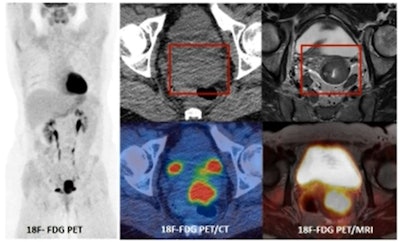

PET/MRI provides a one stop examination for staging cervical cancer due to the superior contrast resolution of MRI compared to CT. All images courtesy of Prof. Vicky Goh, presented at the BIR Annual Congress.

PET/MRI provides a one stop examination for staging cervical cancer due to the superior contrast resolution of MRI compared to CT. All images courtesy of Prof. Vicky Goh, presented at the BIR Annual Congress.Goh, who received the Most Influential Radiology Researcher award in the inaugural EuroMinnies in 2019, said there needed to be changes in the "direction" of PET/MRI.